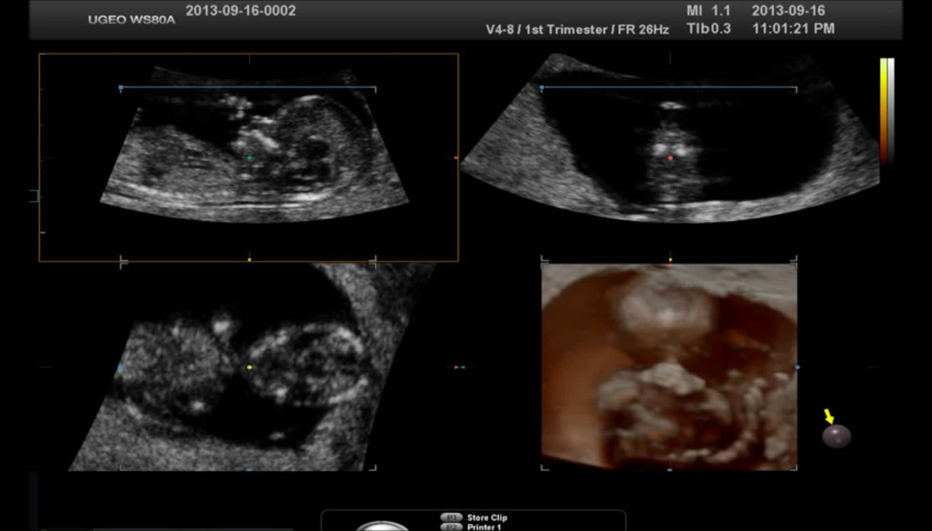

5D NT

从高清容积数据中自动获取正中矢状切面,并智能识别出颈项透明层自动测量,快速、高效、准确地测量胎儿NT。